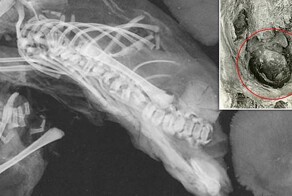

"Кричащую" мумию обнаружили в 1935 году под гробницей архитектора Сенмута, умершего в 1464 году до н.э. В деревянном гробу лежало мумифицированное тело женщины в чёрном парике и с двумя кольцами-скарабеями из серебра и золота, но больше всего археологов поразило выражение её лица.

Рот умершей будто застыл в крике, так её и прозвали "кричащей женщиной".

У женщины отсутствовало несколько зубов (вероятно, она потеряла их перед смертью), а её рост составлял около 1,54 м. По данным компьютерной томографии, на момент смерти ей было около 48 лет, и она страдала от артрита.

Внутри мумии сохранились мозг, диафрагма, сердце, лёгкие, печень, селезёнка, почки и кишечник. Это стало неожиданностью, поскольку классический метод бальзамирования в Новом царстве (550-1069 гг. до н. э.) предусматривал удаление всех этих органов, кроме сердца.